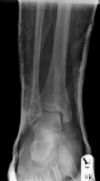

Bimalleolar Ankle Fracture 1/6:: Pre-reduction. AP radiograph